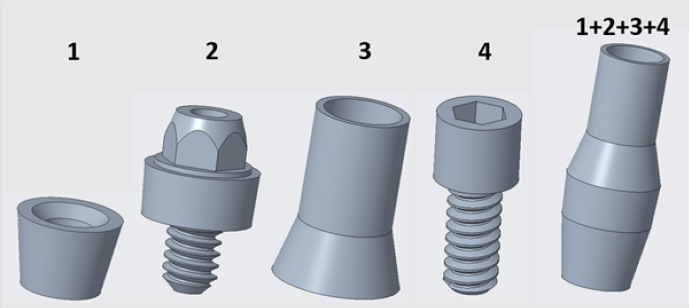

Forces had four points of application on the implant, because dentures were connected to those sites. There were 4 parts between the implant and the denture. 3D models of these connecting components and their assembled state is visible in Figure 5 Component no. 1 was a threaded sleeve that was connected to the baseplate with a welded joint. Component no. 2 was the abutment that had a dual threaded connection with a conical part, which contained a hexagonal fitting geometry for assembly. The height of its lateral wall compensated the necessary gum tissue thickness. This surface was the most crucial part of the system, because it provided epithelial tissue adhesion and bacterial isolation between the oral cavity and tissues. Component no. 3 was the bonded interface containing the base for screw fixation to which the crown was fixed. Part no. 4 was a fixing screw with hexagonal connection. Figure 6 shows our tested implant with occlusal forces and fixation support areas. A sleeve was welded into the implant and the abutment was inserted inside. Fix constraints were chosen because the implant could not move on the bone tissue.